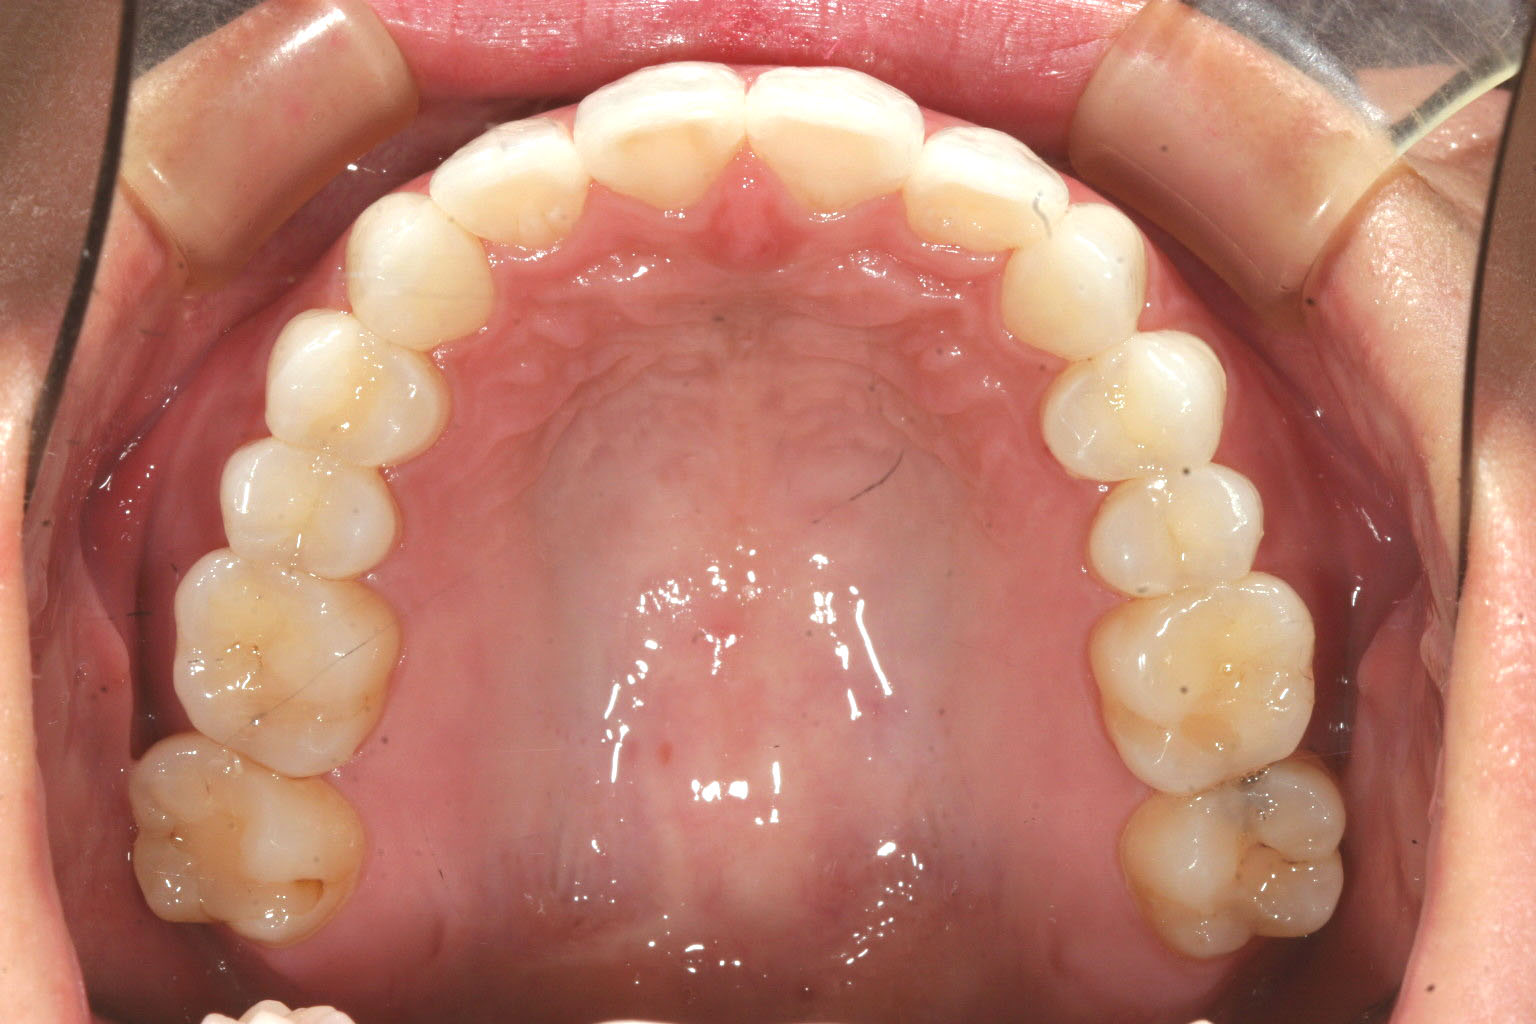

前歯に少しガタガタが見られます。

綺麗に改善してます。